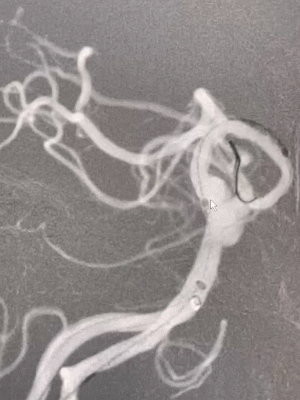

3D造影:基底动脉夹层动脉瘤有多个瘤囊,最大瘤囊4.2*2.7mm,瘤颈较宽。

2